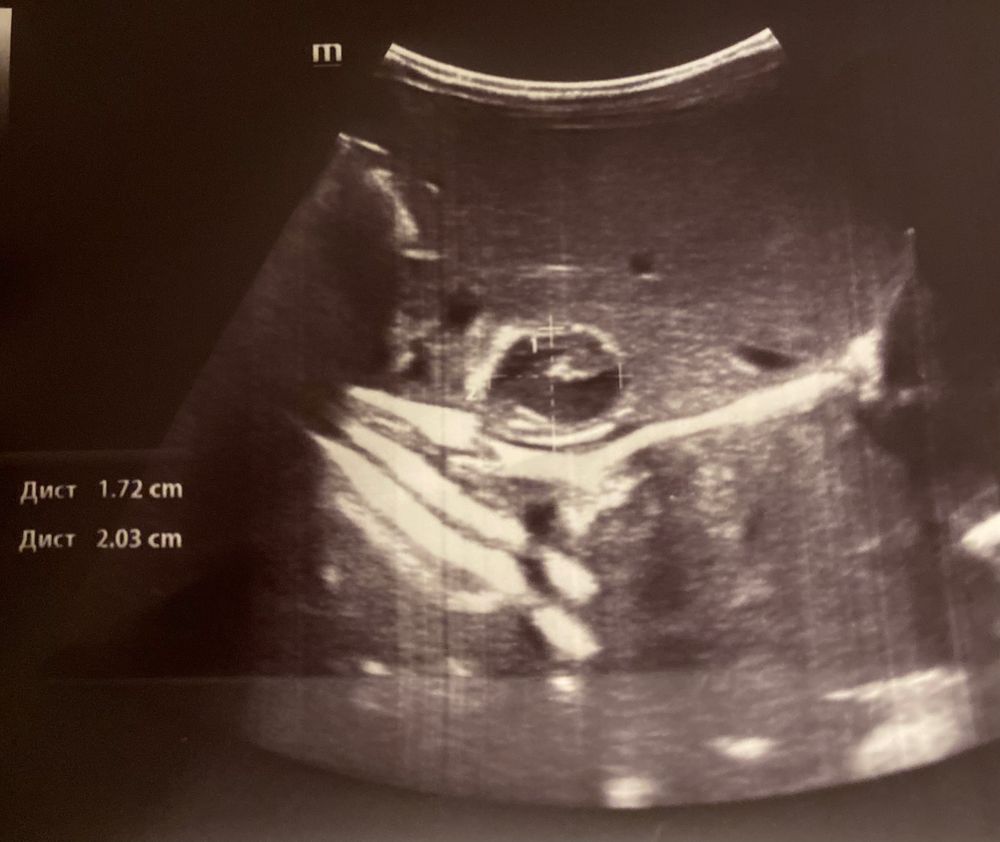

Кровоизлияние в надпочечниках

К трем месяцам кровоизлияние достигло максимальных размеров. Уменьшаться начало после4го месяца. К 10 месяцам рассосалось. У нас было так. К онкологу сходите. Все индивидуально. У нас доросло почти до 10 см.((( Это был из ряда вон выходящий случай. (сейчас все хорошо. Нам скоро 4 года )

Вам стоит сходить на узи снова.